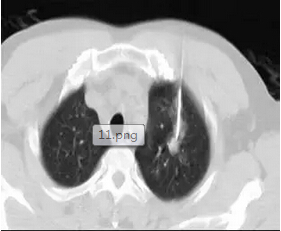

從上圖看患者肺部有嚴(yán)重的肺纖維化、肺大泡,肺功能很不好,左下肺還有一個(gè)3cm左右的腫塊

上圖:我們同樣在CT的引導(dǎo)下把消融針穿入腫瘤內(nèi)部,并獲取了部分腫瘤組織標(biāo)本用于病理定性檢查。

上圖:消融結(jié)束即刻掃描可見(jiàn)沒(méi)有氣胸等損傷。術(shù)后1月增強(qiáng)CT掃描,看到病灶完全沒(méi)有強(qiáng)化。第三位患者因肺癌接受過(guò)分子靶向治療,但一段時(shí)間以后病灶開始有反彈趨勢(shì),他聽病友介紹來(lái)門診咨詢并選擇了微波消融這種治療方法。